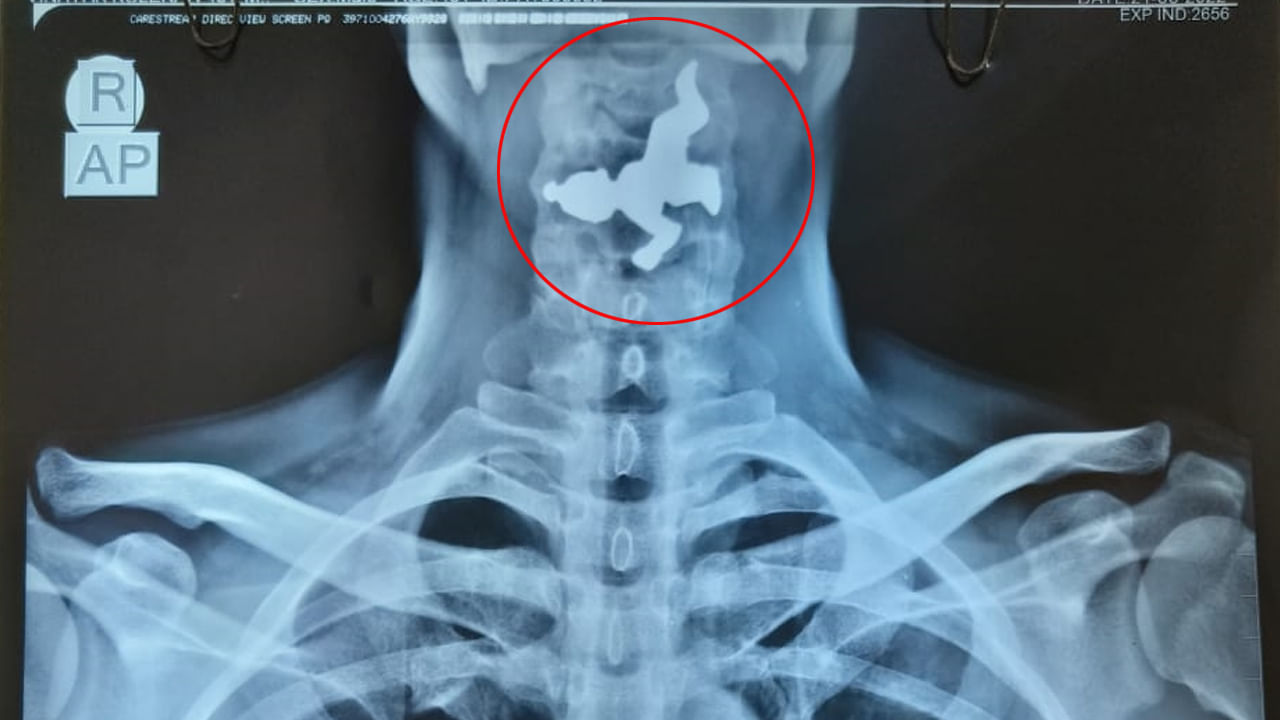

ఈశాన్య ఢిల్లీలోని కకర్తార్ నగర్ ప్రాంతంలో ఈ ఘటన జరిగింది. పదేళ్ల బాలుడు స్టంట్ చేసేందుకు ప్రయత్నిస్తుండగా.. స్కిప్పింగ్ తాడు మెడకు చుట్టుకొని ఊపిరాడక మరణించినట్లు పోలీసులు తెలిపారు. బాలుడు చాలా రకాల స్టంట్ వీడియోలు చూసేవాడని.. అలాగే ఓ వీడియో చూసిన అతను ఒక గదిలోకి వెళ్లాడని పోలీసులు తెలిపారు. స్కిప్పింగ్ చేస్తూ.. స్టంట్ చేయడానికి ప్రయత్నించాడని.. స్కిప్పింగ్ తాడు అతని మెడకు చుట్టుకొని ఊపిరాడక స్పృహతప్పి పడిపోయాడని తెలిపారు. వెంటనే గమనించిన బాలుడి తల్లిబాలుడి తల్లి ఇరుగుపొరుగు వారిని అప్రమత్తం చేసి ఆసుపత్రికి తరలించగా.. అప్పటికే బాలుడు చనిపోయినట్లు వైద్యులు నిర్ధారించారు. ఆసుపత్రి సిబ్బంది పోలీసులకు సమాచారం అందించారు. ఈ ఘటన జరిగిన సమయంలో బాలుడు, తల్లి వేర్వేరు గదుల్లో ఉన్నారని పోలీసులు తెలిపారు. తమ ప్రాధమిక విచారణలో బాలుడి మరణం ప్రమాదవశాత్తూ జరిగిందని గుర్తించామని పోలీసులు తెలిపారు. ఎటువంటి కేసు నమోదు చేయబడలేదని.. CrPC సెక్షన్ 174 (అసహజ మరణం) కింద ఈ ఘటనకు సంబంధించి కేసు దర్యాప్తు చేపట్టామని చెప్పారు.